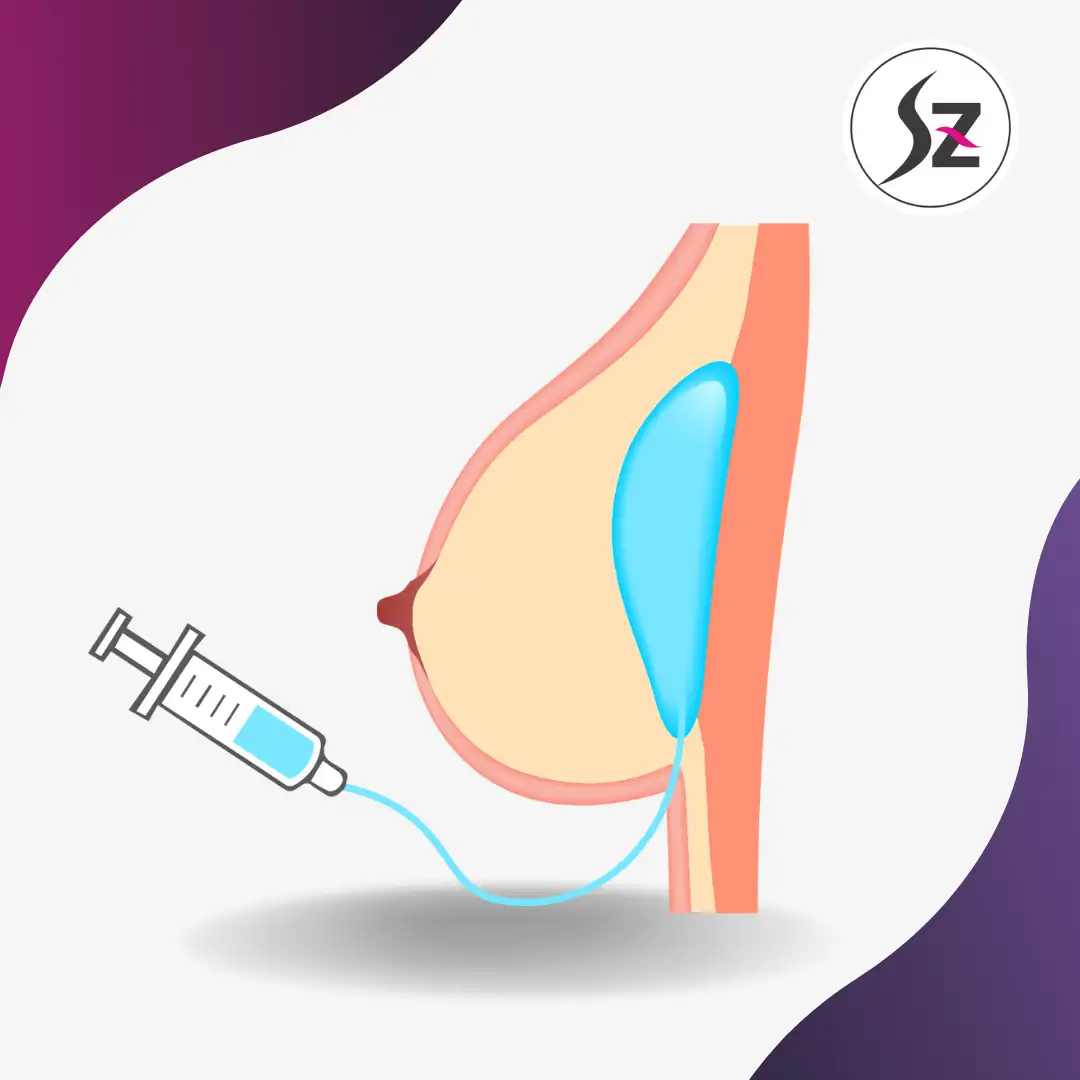

When it comes to breast augmentation, safety, precision, and natural results matter most. Unlike traditional methods that rely solely on endoscopy, 3D laparoscopic Rakoba breast augmentation offers a new level of accuracy and comfort.

Using high-definition endoscopic imaging, surgeons can accurately create the implant pocket while preserving key anatomical structures. The “LakoBar” technique enhances precision, safety, and natural contouring for optimal symmetry and long-term stability.

Unlike conventional breast augmentation, the SZLINE system uses 3D laparoscopic guidance for precise implant placement with minimal scarring (≈2.5 cm) and enhanced accuracy, helping minimize trauma, improve symmetry, and support a more natural breast shape and contour.

Minimally Invasive with a 2.5cm Micro-Incision

With just a tiny 2.5cm incision, the procedure allows for precise implant placement while minimizing scarring.

Enhanced Precision with 3D Laparoscopy

The 3D laparoscopic system provides a clear, magnified view of the surgical area, ensuring accurate implant insertion and natural results.

Safe and Controlled Technique

By inflating the surgical area with CO₂, the surgeon gains space for careful dissection, reducing trauma to surrounding tissues and lowering risks.